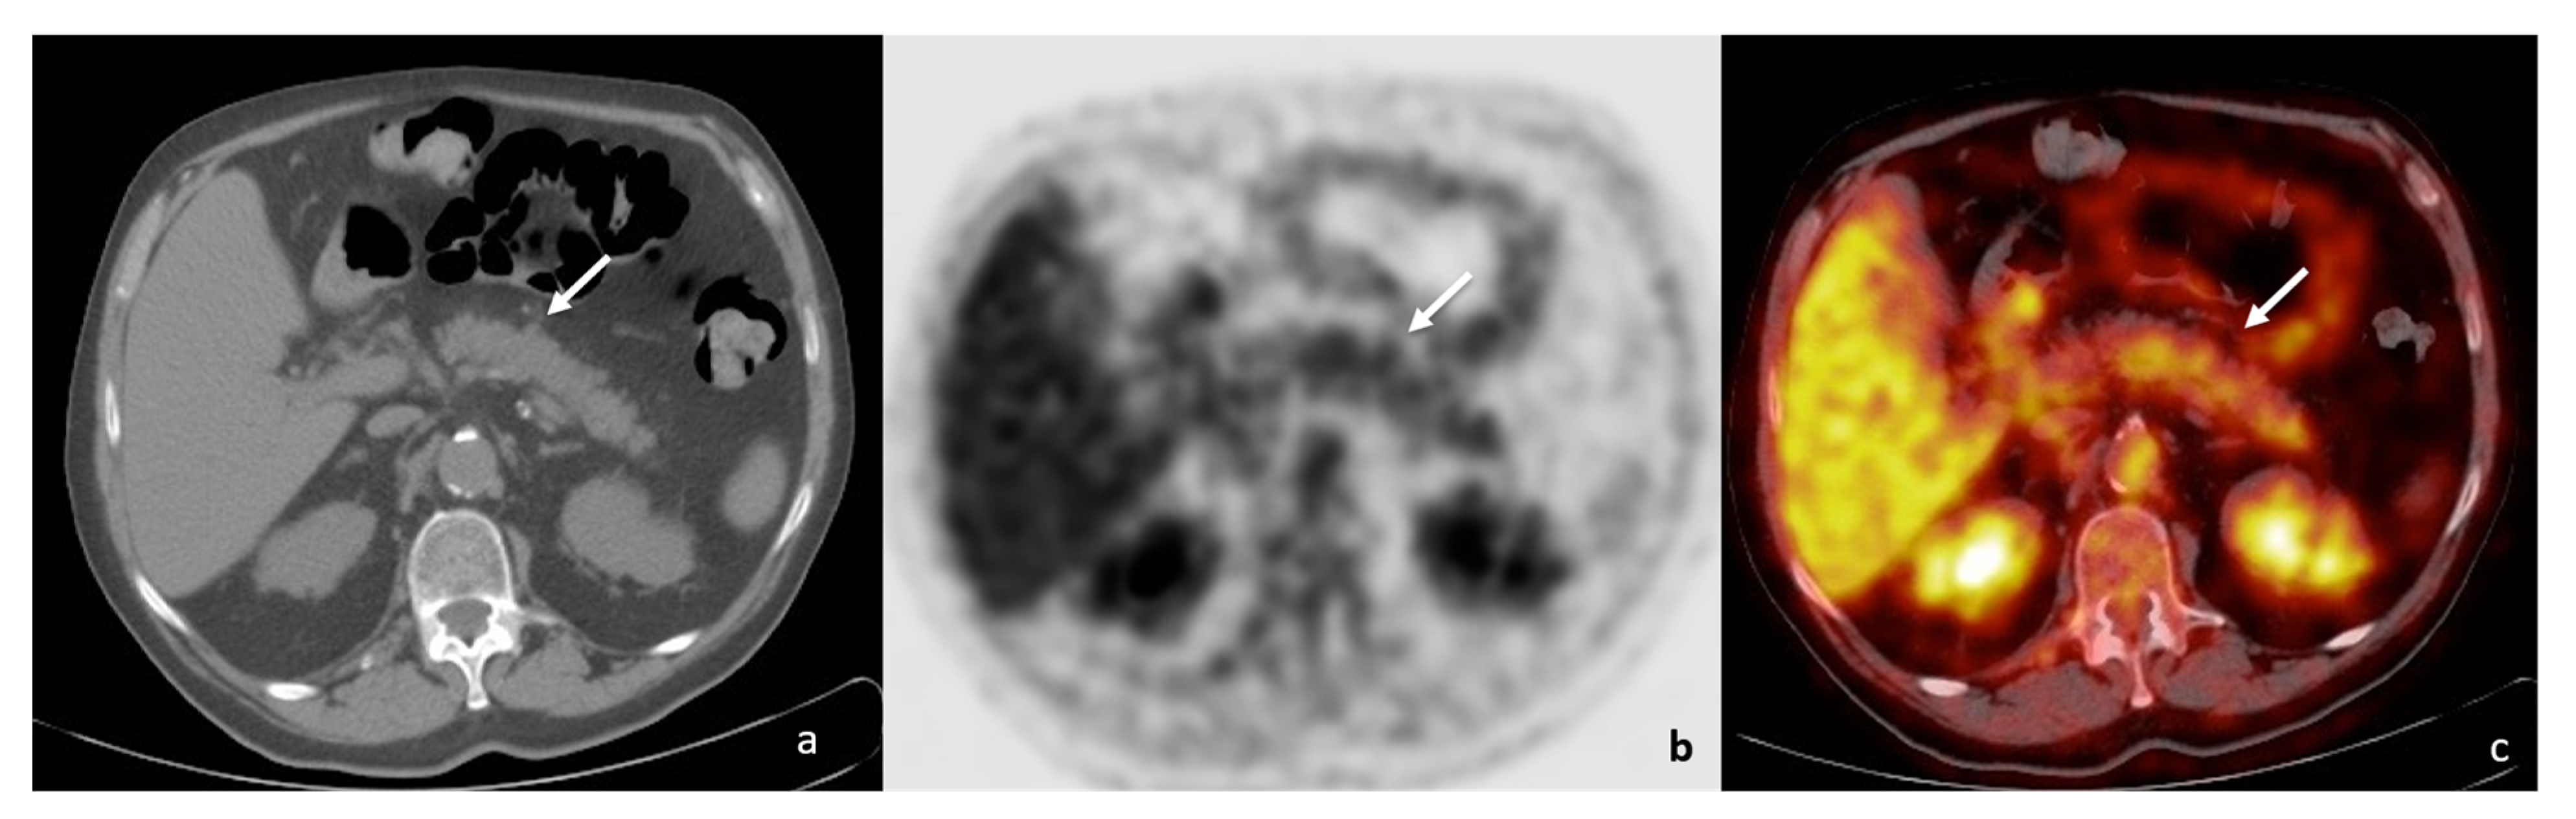

2. Case Report